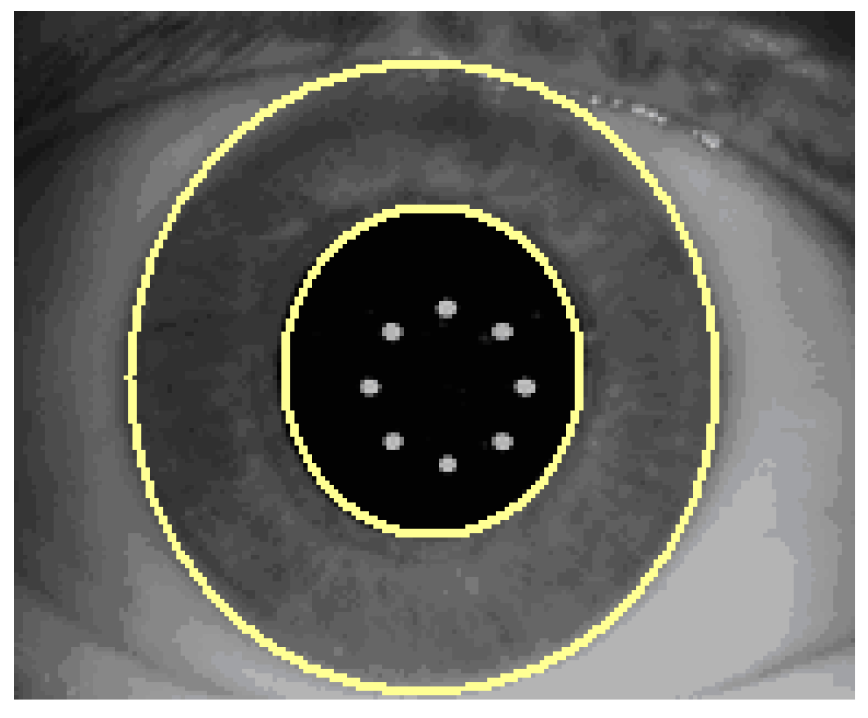

All operations which lead to the final digital iris code are performed within this normalized band (Figure 7).

Within this band of iris image data, a unique digital code is generated. The basic data stream of this digital code consists of information obtained at 980 different iris locations. This iris code is, therefore, a unique code for this specific iris pattern and is used to detect potential torsional deviations between two different images from the same iris. The output parameters of the rotational eye tracker system—such as pupil radius/center and limbus radius/center—are given in resolution less than 30 µm. The rotation angle between images is within ±14.8° and with the resolution of 0.7° (=360°/512). Response time is 40 ms (i.e., 25 Hz).

Figure 7. Digital iris code performance.